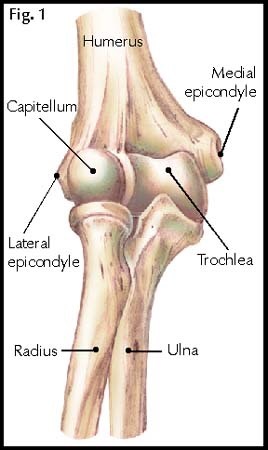

If there is injury to rotator cuff muscles, what is the likely order in which the muscles will be torn

SITS

What rotator cuff muscle is responsible for abduction of shoulder

supraspinatous

Which rotator cuff muscle is responsible for internal rotation of shoulder

subscapularis

Which muscles are responsible for external rotation of shoulder